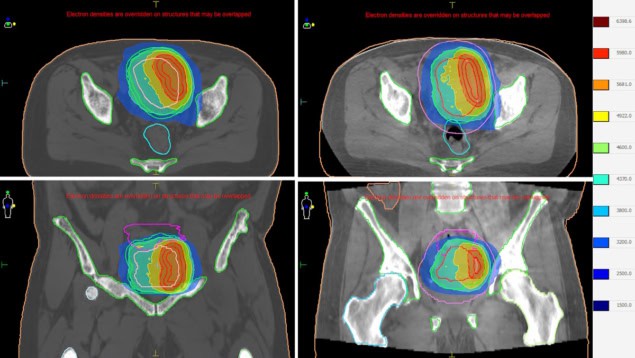

The workflow begins with patient positioning and CBCT imaging, with Evo’s AI-enhanced Iris imaging significantly improving image quality, crucial when performing ART. The radiation therapist then matches the cone-beam and planning CTs and performs any necessary couch shift.

Simultaneously, Elekta ONE Online performs AI auto-contouring of OARs, which are reviewed by the physician, and the target volume is copied in. The physicist then simulates the dose distribution on the new contours, followed by a plan review. “Then you can decide whether to adapt or not,” says Lampe. “This is an outstanding feature.” The final stage is treatment delivery and online dosimetry.

Houweling says that ART delivery has taken 19 minutes on average. “We record the CBCT, perform image fusion and then the table is moved, that’s all standard,” she explains. “Then the adaptive part comes in: delineation on the CBCT and creating a new plan with Elekta ONE Planning as part of Elekta One Online.”

The plan adaptation, when selected to perform, takes roughly four minutes to create a clinical-grade volumetric-modulated arc therapy (VMAT) plan. With the soon to be installed next-generation optimizer, it is expected to take less than one minute to generate a VMAT plan.